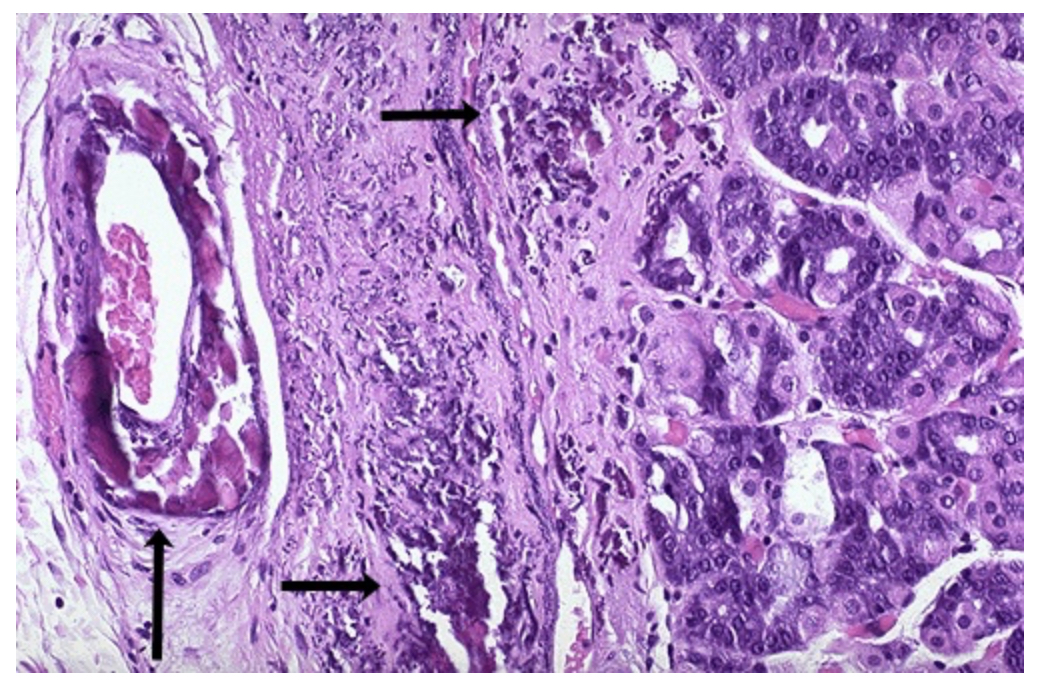

Histological Section of the Liver containing cytoplasmic organelle damage. Identify the red globular material encircled. Identify type of intracellular accumulation.

Mallory Bodies. Protein Accumulation